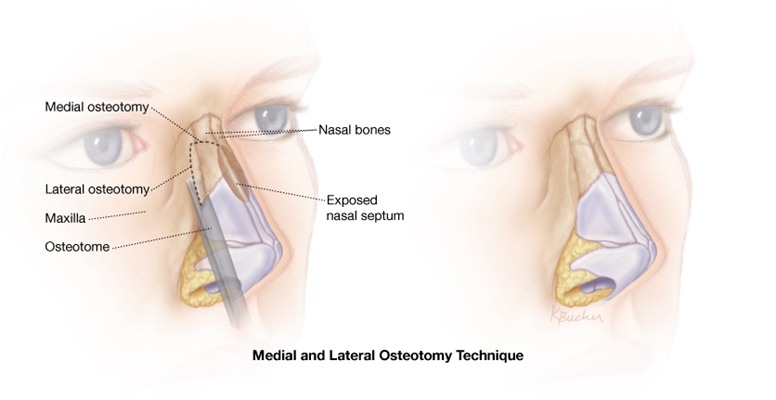

A:鼻中隔偏曲手術分為局麻下手術、全麻下手術,手術方式包括鼻中隔軟骨膜下切除術或者是三線減張術。局麻下手術費用約在5500-6500元,全麻下手術較局麻下手術要貴1500-2000元。鼻中隔偏曲如果伴有持續性的單側鼻塞,用藥效果不顯著、引起鼻……

A:鼻中隔偏曲是在鼻內鏡下進行鼻中隔矯正術,這種手術可以打局部麻醉,鼻內鏡手術是一種微創手術,創傷小,恢復快,痛苦少。如果患者對疼痛比較敏感,不能耐受,可以考慮打全身麻醉。術後由於鼻腔塞有紗布,患者會出現鼻子無法呼吸,要改用口腔呼吸,所以會……